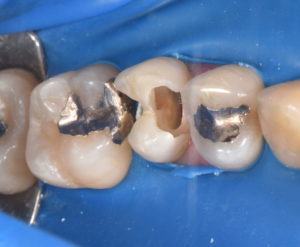

左上小臼歯部に歯髄に近接した深在性のう蝕をみとめる。痛み等の症状はないため歯髄の保存を試みることとした。

ラバーダム防湿を行い、唾液からの保護を行った後、う蝕を除去していくと容易に歯髄が露出した。炎症性の冠部歯髄を除去し、マイクロスコープ強拡大下で断髄面の状態を確認したところ正常な血管の走行を認めたため、MTAセメントを用いて歯髄保護を行った。